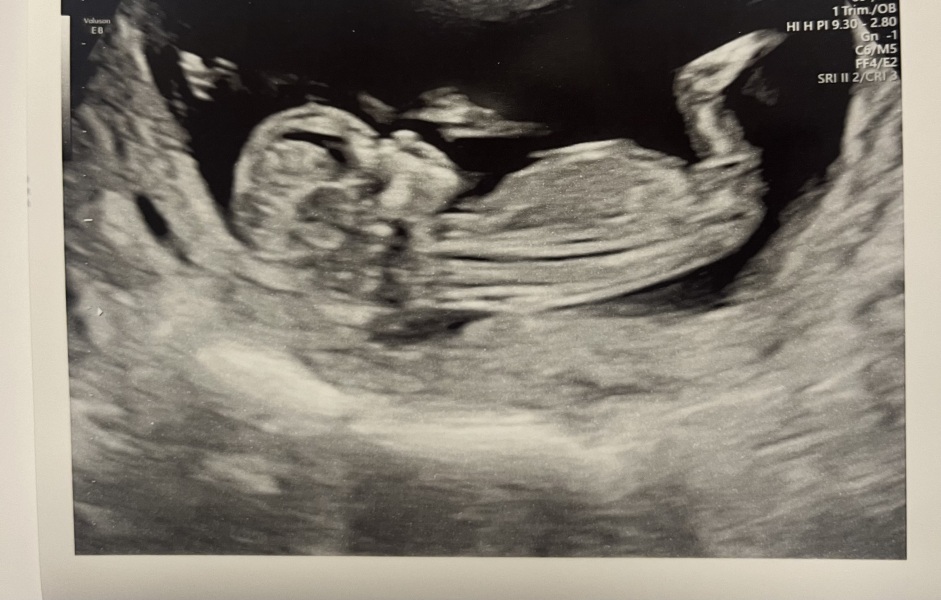

Scan went well 🥺 baby is measuring ahead at 12+4 due October 6th 🥰

Im so happy - it feels so surreal! Xxx